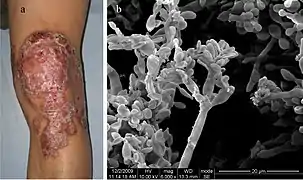

Chaetothyriomycetidae is a subclass of ascomycete within the class Eurotiomycetes. Many species in Chaetothyriomycetidae are lichens.

Gallery